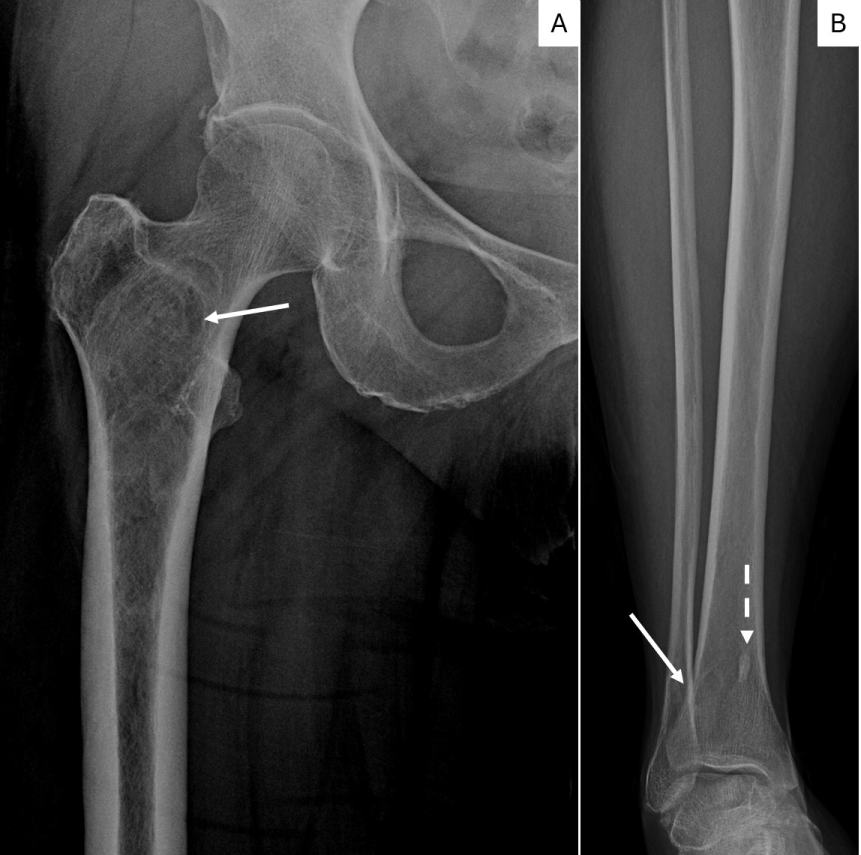

A 55-year-old woman presented to our tertiary care facility referred from an outside institution after a 3 cm mass in her left breast was identified (Figure 1). The mass was biopsied, and she was subsequently diagnosed with a high grade invasive ductal carcinoma (IDC) (Figure 2). The cancer was negative for estrogen receptor, progesterone receptor and Her2. Additionally, the proliferative rate as assessed by Ki-67 was 85 percent. An axillary lymph node was suspicious by imaging, but not biopsied. A nuclear medicine bone scan with a Tc-99 m radiotracer was used to stage her cancer (Figure 3). The imaging showed increased radiotracer uptake in the right proximal femur and right distal tibia suggestive of metastases and therefore, the patient was considered to have stage IV metastatic breast carcinoma. However, radiographs of the right femur and tibia showed stable lesions without aggressive cortical involvement and a ground glass appearance suggestive of fibrous dysplasia (Figure 4A and 4B). A subsequent biopsy of the proximal femur lesion showed atypical fibrous tissue with S-shaped woven bone trabeculae that tested negative for MDM2 amplification, essentially ruling out low grade osteosarcoma which can sometimes histologically mimic FD [11] and confirming the imaging impression of fibrous dysplasia (Figure 5). Additional genetic testing showed that the fibrous dysplasia was caused by a somatic mutation on codon 201 of the GNAS gene, substituting cytosine in CGT for thymine (TGT). As the fibrous dysplasia was found incidentally as part of the patient’s metastatic work up and was generally asymptomatic, it was clinically followed. Her triple negative breast cancer responded to preoperative chemotherapy, and a subsequent left breast segmental mastectomy showed only treatment related changes and no residual disease. The sentinel lymph nodes were negative for metastatic carcinoma. The breast specimen was evaluated by molecular sequence analysis which revealed no mutation in exon 8 or 9 of the GNAS gene. The patient is currently well with stable polyostotic fibrous dysplasia and without residual carcinoma.

Figure 4: Figure 4a. X-ray of the right femur shows a intramedullary intertrochanteric/subtrochanteric lesion in the right femur with minimal expansion of proximal diaphysis without aggressive cortical involvement. Sclerotic rim, minimal expansion and ground glass appearance suggest Fibrous Dysplasia. (arrow).

4b. X-ray of the tibia shows a metaphyseal osteolytic lesion with smooth to sclerotic rim of FD in right distal tibia superimposed with normal trabeculae (white arrow). A bone island is also present in the medial tibia (dashed arrow). View Figure 4